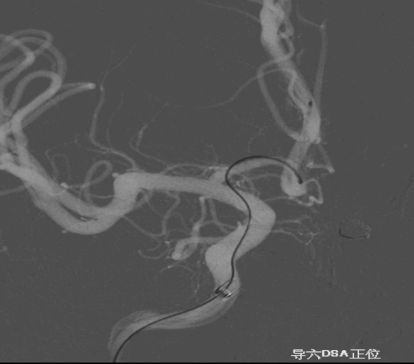

术后正侧位造影:Raymond Ⅲ级

术后支架重建:支架打开良好,近端Marker位于颈内动脉分叉处

术后Vaso CT未见出血,患者神清语利,神经系统查体阴性。